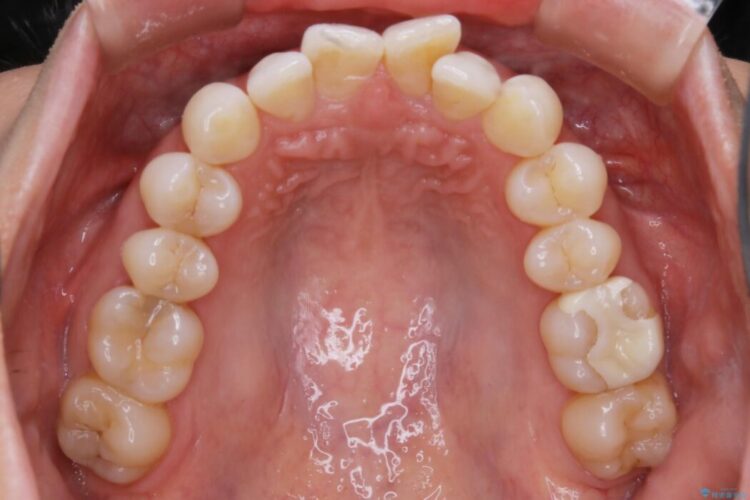

治療計画を立てる上で詳しく精密検査をしたところ、左下の6番目の歯につきまして治療が必要な状態であることが分かり、かぶせ物を外し、内部を確認しました。

結果としては深い部分で根が破折してしまっていました。

破折の処置としては基本的に抜歯が選ばれます。

悪くなっている歯の放置はできないと判断しましたので、患者様と様々な治療プランを相談した上で、最終的に該当の歯は抜歯をして噛み合わせを改善し、その後インビザラインでの矯正治療を行うこととしました。